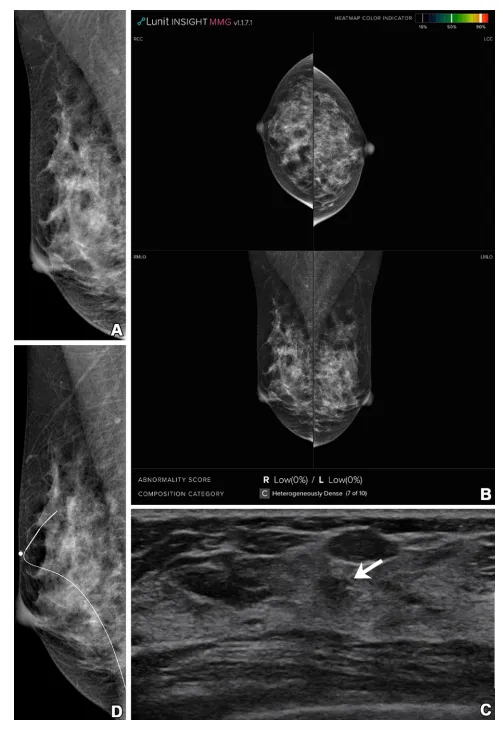

Figure 3: Imaging in a 41-year-old woman with heterogeneously dense breasts (Breast Imaging Reporting and Data System category c). (A, B) Right mediolateral oblique digital mammogram (A) and right and left craniocaudal (RCC, LCC) and right and left mediolateral oblique (RMLO, LMLO) mammograms with artificial intelligence (Lunit INSIGHT MMG, version 1.1.7.1; Lunit) (B) show no abnormality. © Supplemental transverse US image shows a 1.0-cm irregular mass (arrow) in the right breast. (D) Right mediolateral oblique digital mammogram after US-guided wire localization shows no suspicious findings, even in retrospect. The radiopaque round marker, which is attached on the skin to mark the wire insertion site, is visible. The patient was treated with breast-conserving surgery, and the mass was proven to be invasive ductal carcinoma (pT1N0, 0.7 cm in size, estrogen receptor and progesterone receptor positive, human epidermal growth factor receptor 2 negative, histologic grade 1).

图3: 影像显示一名41岁乳腺结构异质性致密的女性(乳腺影像报告与数据系统分类c)。(A, B) 右侧中斜位数字乳腺X线照片 (A) 和右侧及左侧头尾位 (RCC, LCC) 以及右侧及左侧中斜位 (RMLO, LMLO) 乳腺X线照片使用人工智能(Lunit INSIGHT MMG,版本1.1.7.1;Lunit)辅助 (B) 显示未见异常。© 补充横断面超声图像显示右乳房有一个1.0厘米的不规则肿块(箭头)。(D) 超声引导下的导丝定位后的右侧中斜位数字乳腺X线照片在回顾时仍未显示可疑发现。附着在皮肤上的不透明圆形标记可见,用于标记导丝插入部位。患者接受了乳腺保留手术,肿块被证实为浸润性导管癌(pT1N0,大小0.7厘米,雌激素受体和孕激素受体阳性,HER2阴性,组织学等级为1)。